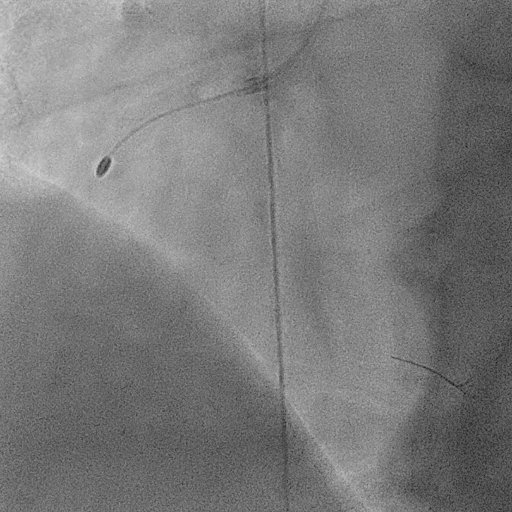

Herzkatheter in Aktion: Einblick in die Gefäße

Um den Ablauf einer Stent-Implantation besser zu veranschaulichen, zeigen wir Ihnen hier, wie die Herzkranzgefäße vor und nach der Behandlung aussehen. Die Aufnahmen stammen aus der Live-Durchleuchtung während des Eingriffs und geben Ihnen einen echten Einblick in die Funktionsweise des Herzkatheters. Diese Aufnahmen verdeutlichen, wie der Stent das Gefäß sofort entlastet und die Durchblutung wiederherstellt.

2. Der freie Blutfluss (nach der Behandlung)

Nachdem der Stent platziert wurde, ist das Gefäß wieder vollständig geöffnet. Das zweite Video zeigt, wie das Blut nun ungehindert durch das Gefäß fließen kann.